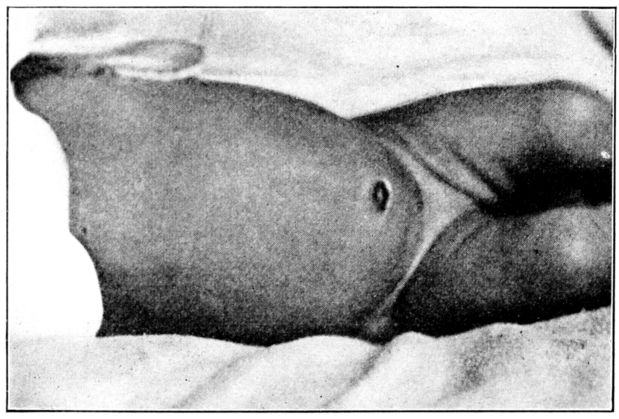

| 140. | Baby partially blind as a result of a faulty diet | 378 |

| 141. | Rachitic and normal babies of the same age | 381 |

| 142. | Chest walls of normal and rachitic rats of the same age | 383 |

| 143. | Interior of specimens in Fig. 142 | 384 |